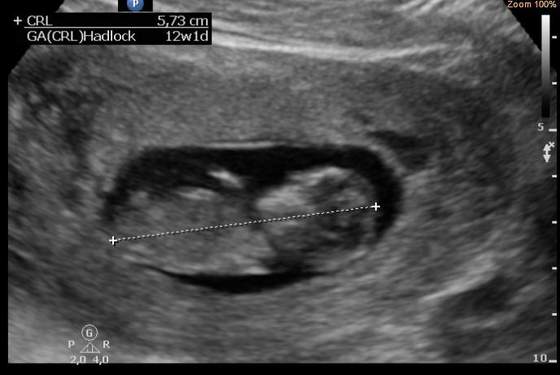

Jutro wkleję dwa zaległe zdjęcia i może trzecie świeże